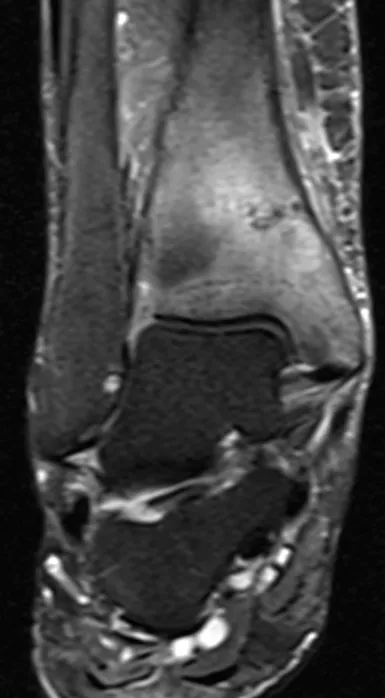

Stress fracture Radiology Images

Browse 4 medical images tagged with stress fracture. This collection includes various imaging modalities for medical education and reference.

About Stress fracture Imaging

- This collection contains 4 radiology images related to stress fracture, including various imaging modalities such as X-rays, MRIs, CT scans, and ultrasound images commonly used in medical diagnosis and education.